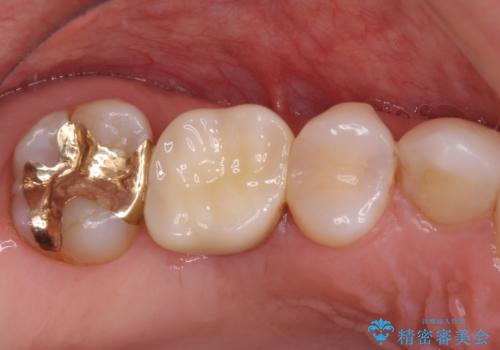

抜歯になった虫歯 奥歯のインプラント治療

強い咬み合わせで割れてしまった奥歯 インプラントによる咬合回復

虫歯による歯の喪失 インプラントによる咬合機能回復